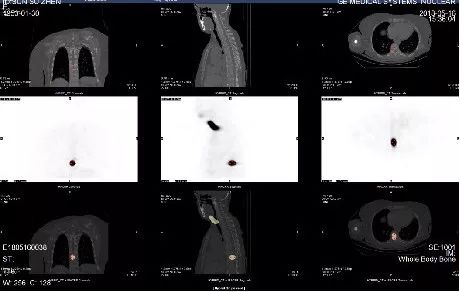

肺转移:甲状腺癌发生肺转移,根据转移灶的大小、多少及分布情况不同有多种表现。多发小结节肺转移癌碘-131治疗效果最好,患者经过多次治疗能达到临床治愈目的。比如下面这个甲状腺弥漫性肺转移的病人经过3次碘-131治疗,肺部病灶几近消失。

甲状腺癌肺转移

骨转移:碘-131对骨转移病灶治疗的疗效虽不如肺转移,但通过治疗可以控制病灶进展,缓解局部症状,从而提高生活质量,延长生存期。

甲状腺癌骨转移